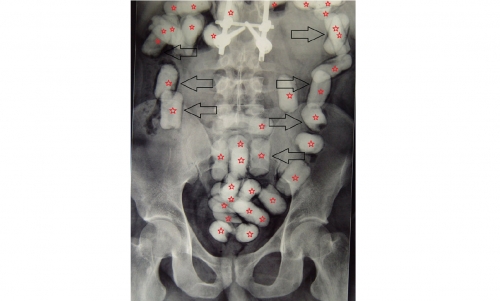

He was redirected to the red channel for a thorough check, where X-ray imaging revealed multiple round objects concealed inside his abdomen, believed to be drug capsules.

He subsequently expelled 42 yellow capsules, followed shortly by an additional 16.

After being transferred to the hospital, he released 28 more, and later 14 additional capsules — bringing the total to 100 capsules in three separate batches.